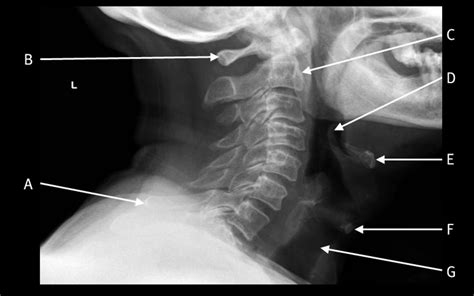

A Soft Tissue Neck Xray is a medical imaging technique that uses low-dose X-rays to produce images of the soft tissues in the neck region. Unlike traditional X-rays that focus on bones, a soft tissue X-ray is designed to visualize structures such as muscles, tendons, and ligaments. This makes it an invaluable tool for diagnosing conditions that do not involve bone abnormalities.

Interpreting the results of a Soft Tissue Neck Xray requires expertise in radiology. The radiologist will examine the images for any abnormalities, such as:

• soft tissue neck anatomy xray